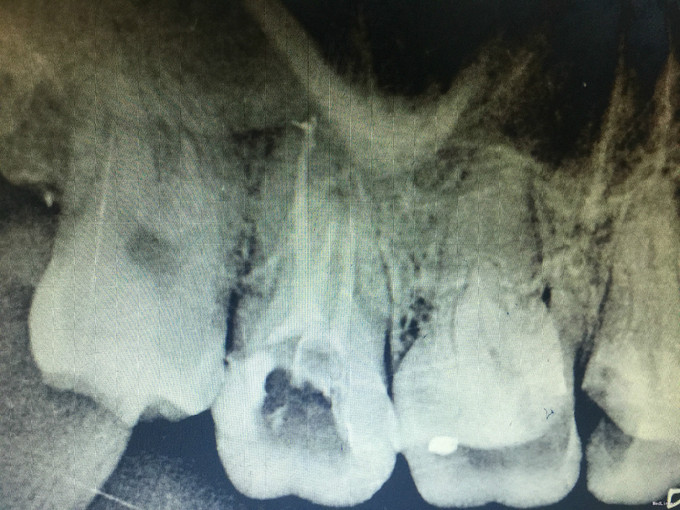

临床检查:17远中及牙合面充填物未脱落,探(+-),冷(+-),叩(-),松动度(-),牙周正常. 辅助检查:X线示17龋坏近髓腔。

诊断:17继发龋 治疗:经患者知情同意后,17局麻去除原有充填物降牙合,开髓拔髓寻找根管口,建立直线通路,扩通根管,确定工作长度。S3/EDTA凝胶镍钛器械,低浓度次氯酸钠冲洗根管,预备至35/04,氢氧化钙诊间封药,一周后复诊,试主尖X线示恰充,试干根管,导AH-PLUS糊剂,VDW热压胶垂直加压根充,术后见根管恰充,暂封调合抛光。术后观察嵌体修复。